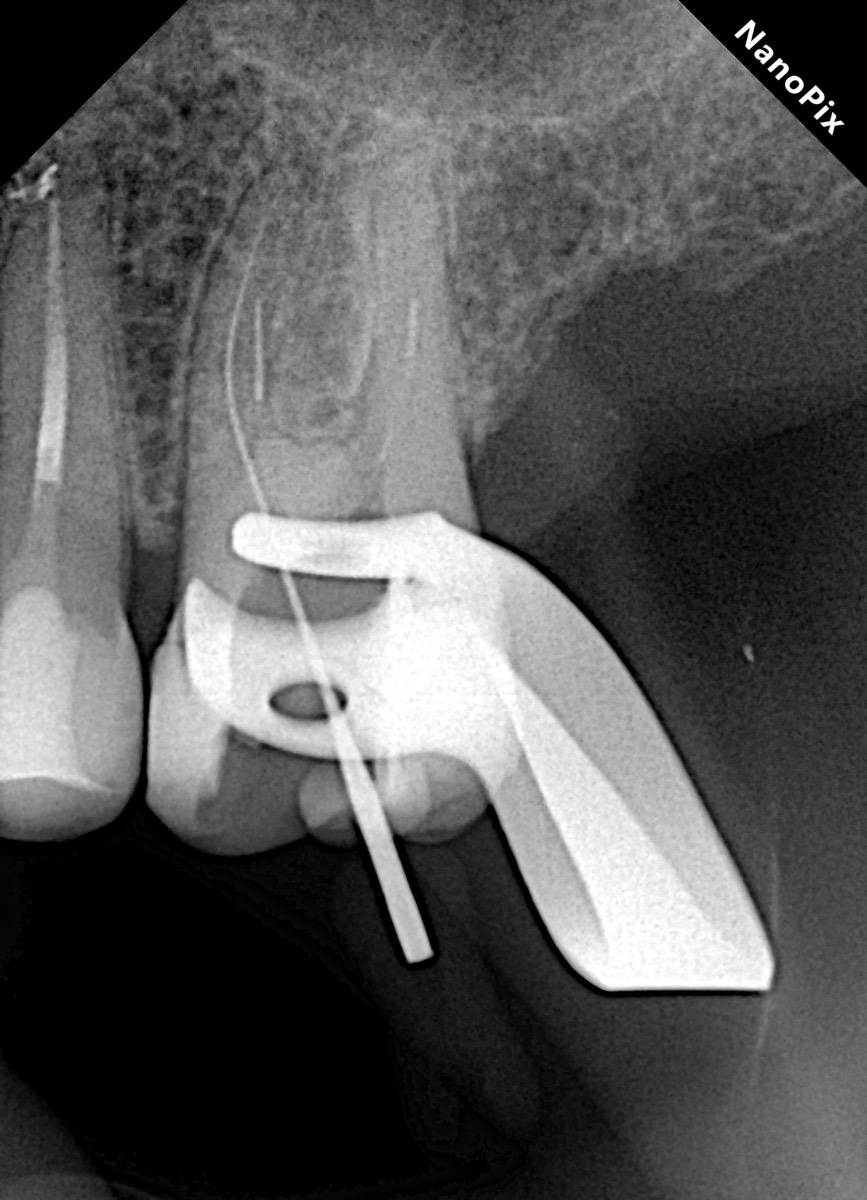

Гарриевич Опубликовано 31 января Автор Поделиться Опубликовано 31 января Когда в твоем кресле оказывается пациент с редким заболеванием «стоматолог-терапевт» работать всегда… легче. Именно! Потому что ты на 100% уверен, что этот человек понимает разницу между «гарантия» и «прогноз», а он на 100% уверен, что ты тот кто ему нужен. Зуб 4.7 со сложной анатомией, ступенькой в мезиальной системе, двойным изгибом, пропущенным каналом и апикальным периодонтитом. Реколл 1 год И сам осмотр через 1 год 4 1 1 Ссылка на комментарий

Carioznik Опубликовано 31 января Поделиться Опубликовано 31 января Наконечник для ручных файлов для чего использовали (для ступени)? А то, у меня где-то пылится такой, я и забыл про него... Ссылка на комментарий

Гарриевич Опубликовано 2 февраля Автор Поделиться Опубликовано 2 февраля @Carioznik да, им проще сглаживать ступень, проходить длинные каналы, в дистальном отделе удобнее фиксировать файл 1 1 Ссылка на комментарий